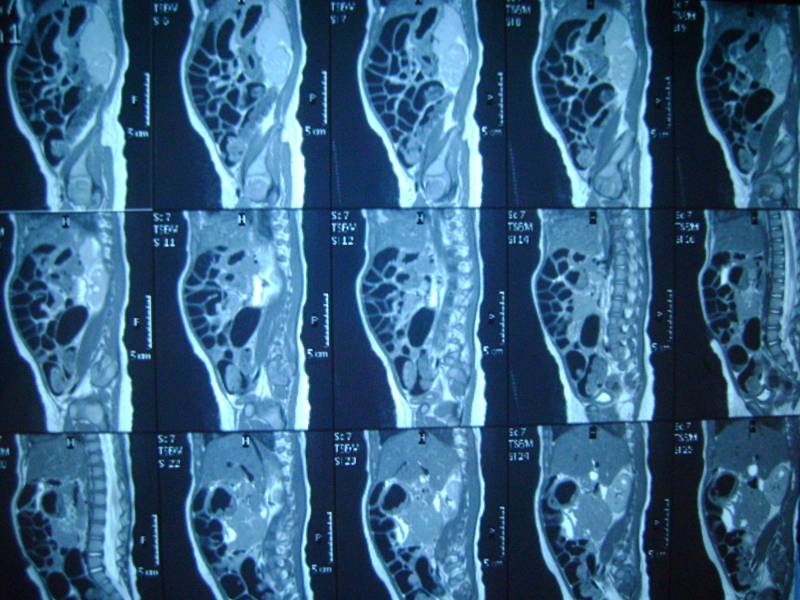

еще